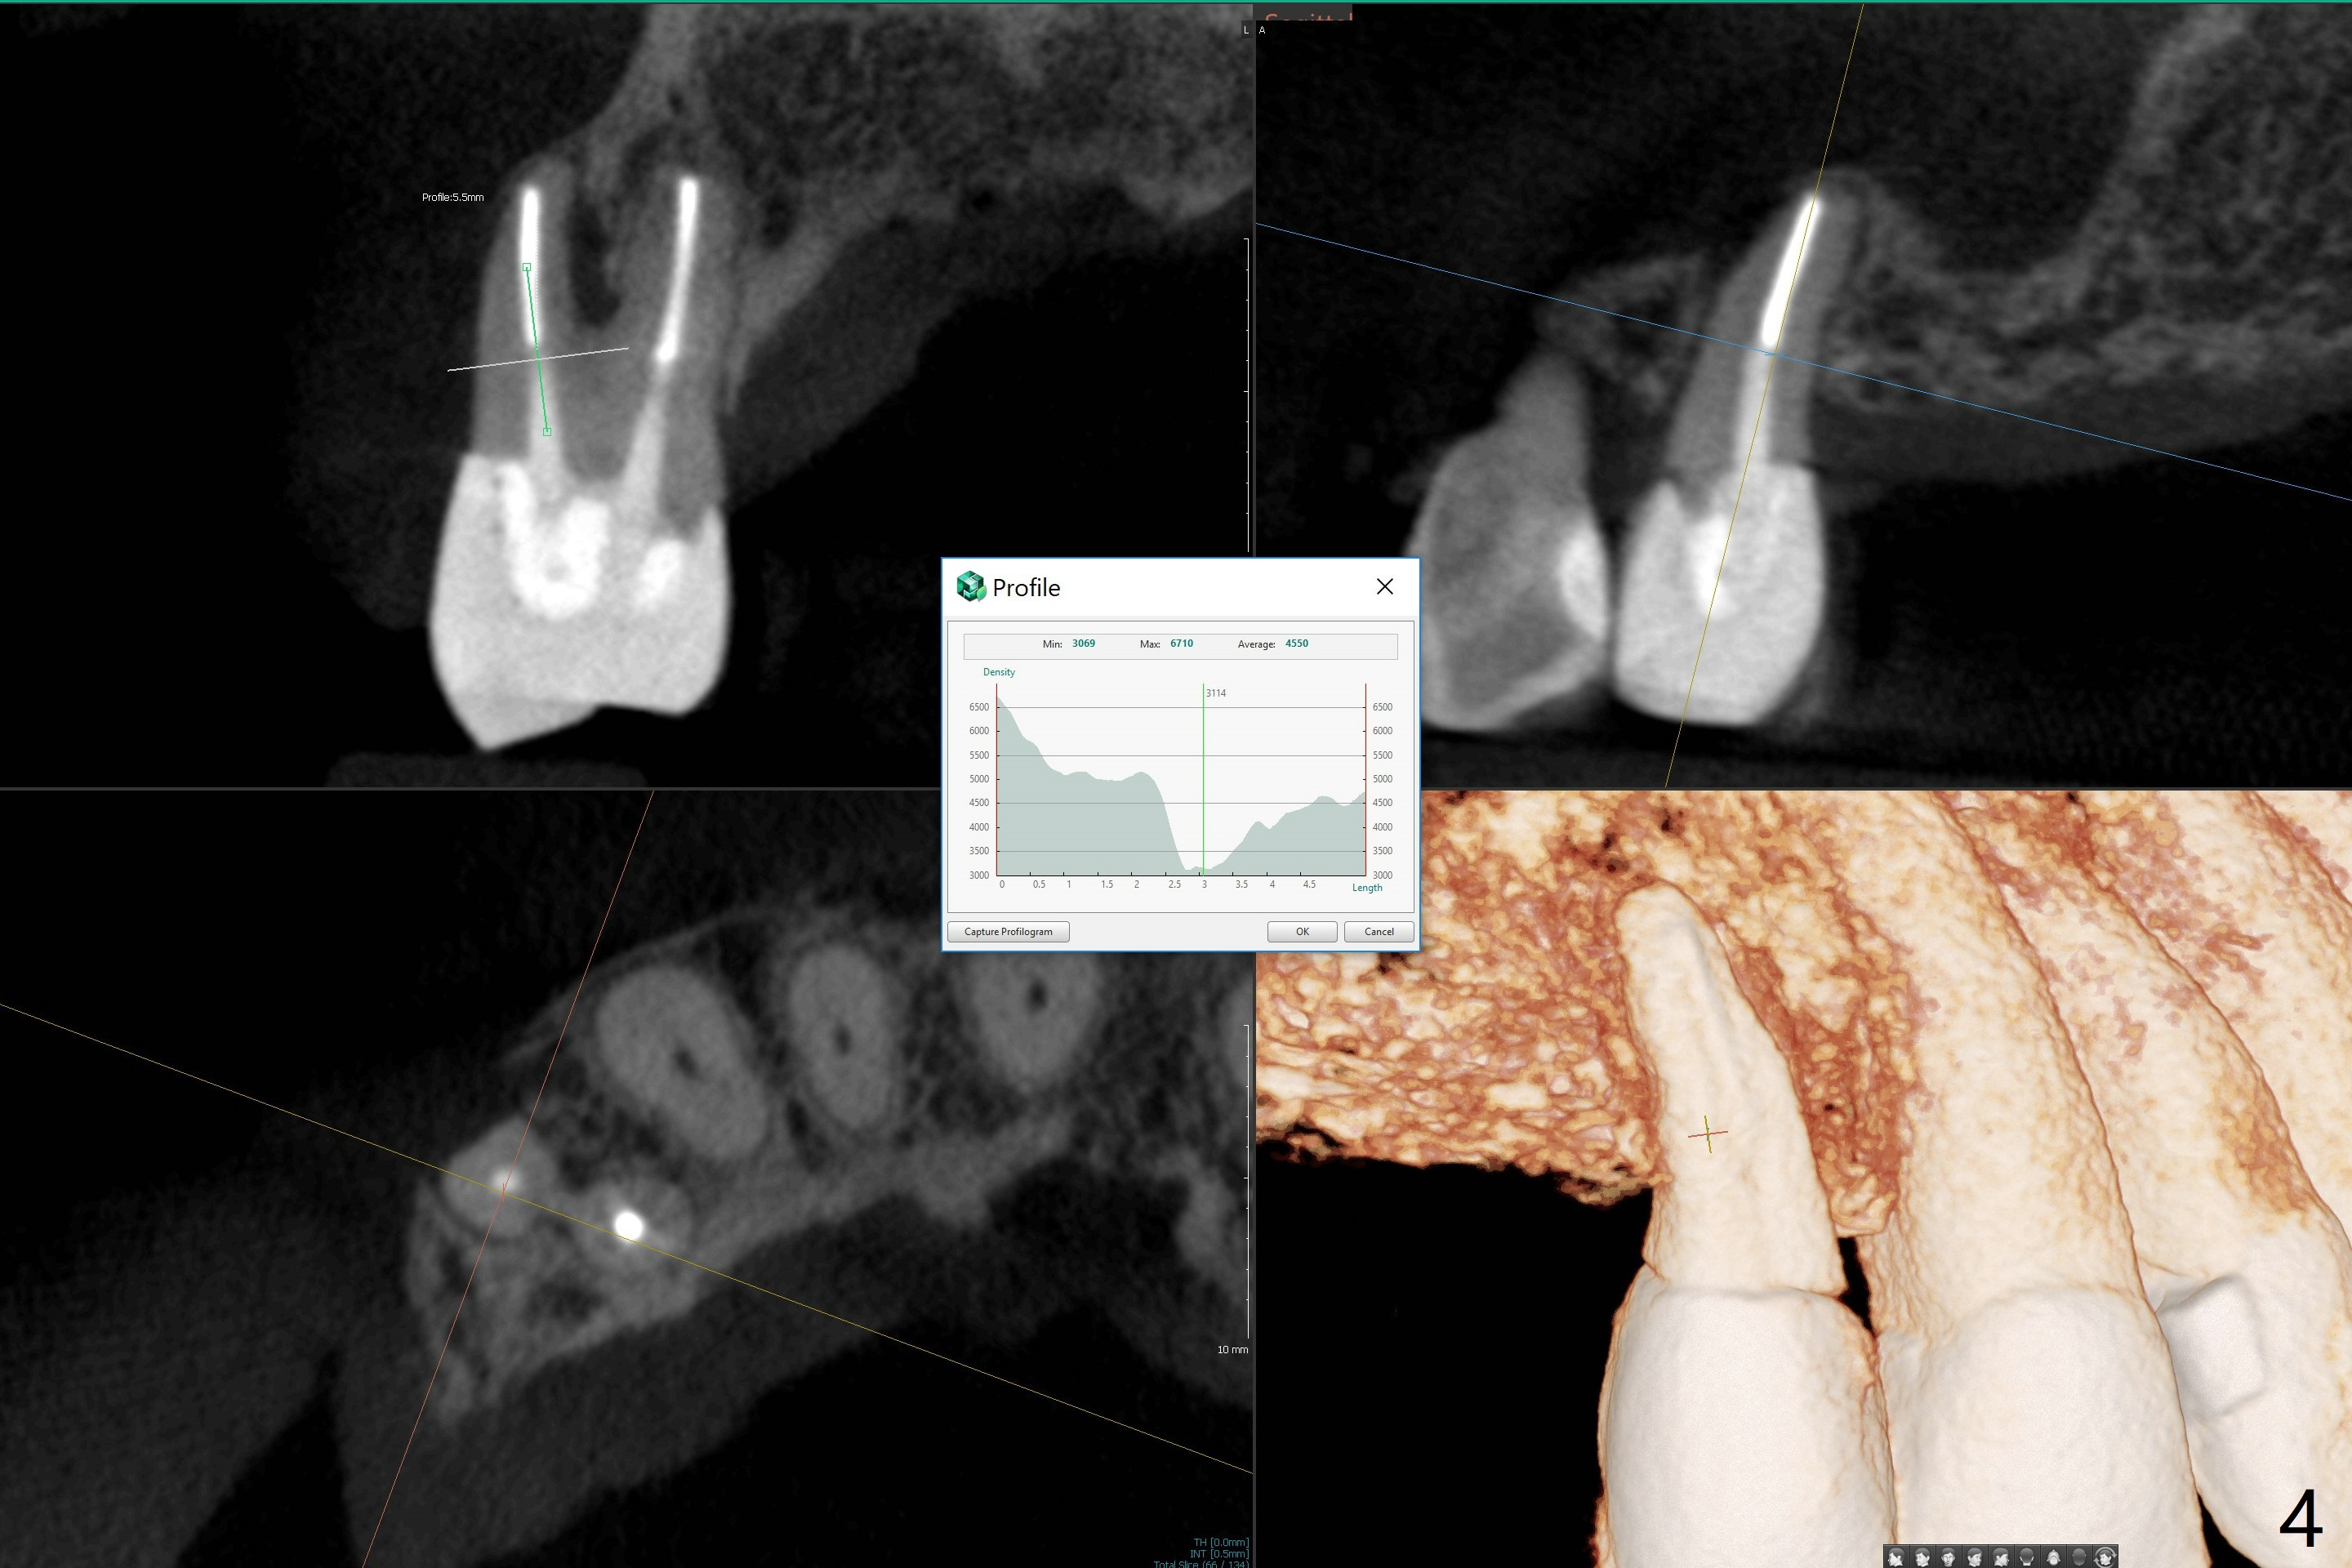

A 71-year-old woman with RPDs develops a fistula buccal to the tooth #5 (Fig.1). The buccal root seems to be fractured as indicated by arrowheads in Fig.2,3 (coronal and sagittal sections). The diagnosis of the fracture is confirmed by the abrupt change in density shown in Profile and the coronal section in Fig.4. Three-dimensional image demonstrates bone over the root surface of the teeth 6 and 8 (Fig.5 *), as compared to no bone over the the buccal root of the tooth #5. Due to financial constraint, the buccala root amputation is proposed as a treatment option. Is it viable?